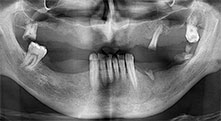

Dentition résiduelle

Un patient de 40 ans dont la dentition naturelle était en très mauvais état voulait une restauration par implants. Étant fumeur, une élévation sinusienne dans le maxillaire avec prothèse fixe était contre-indiquée. Une prothèse avec barre sur quatre implants antérieurs a été programmée.